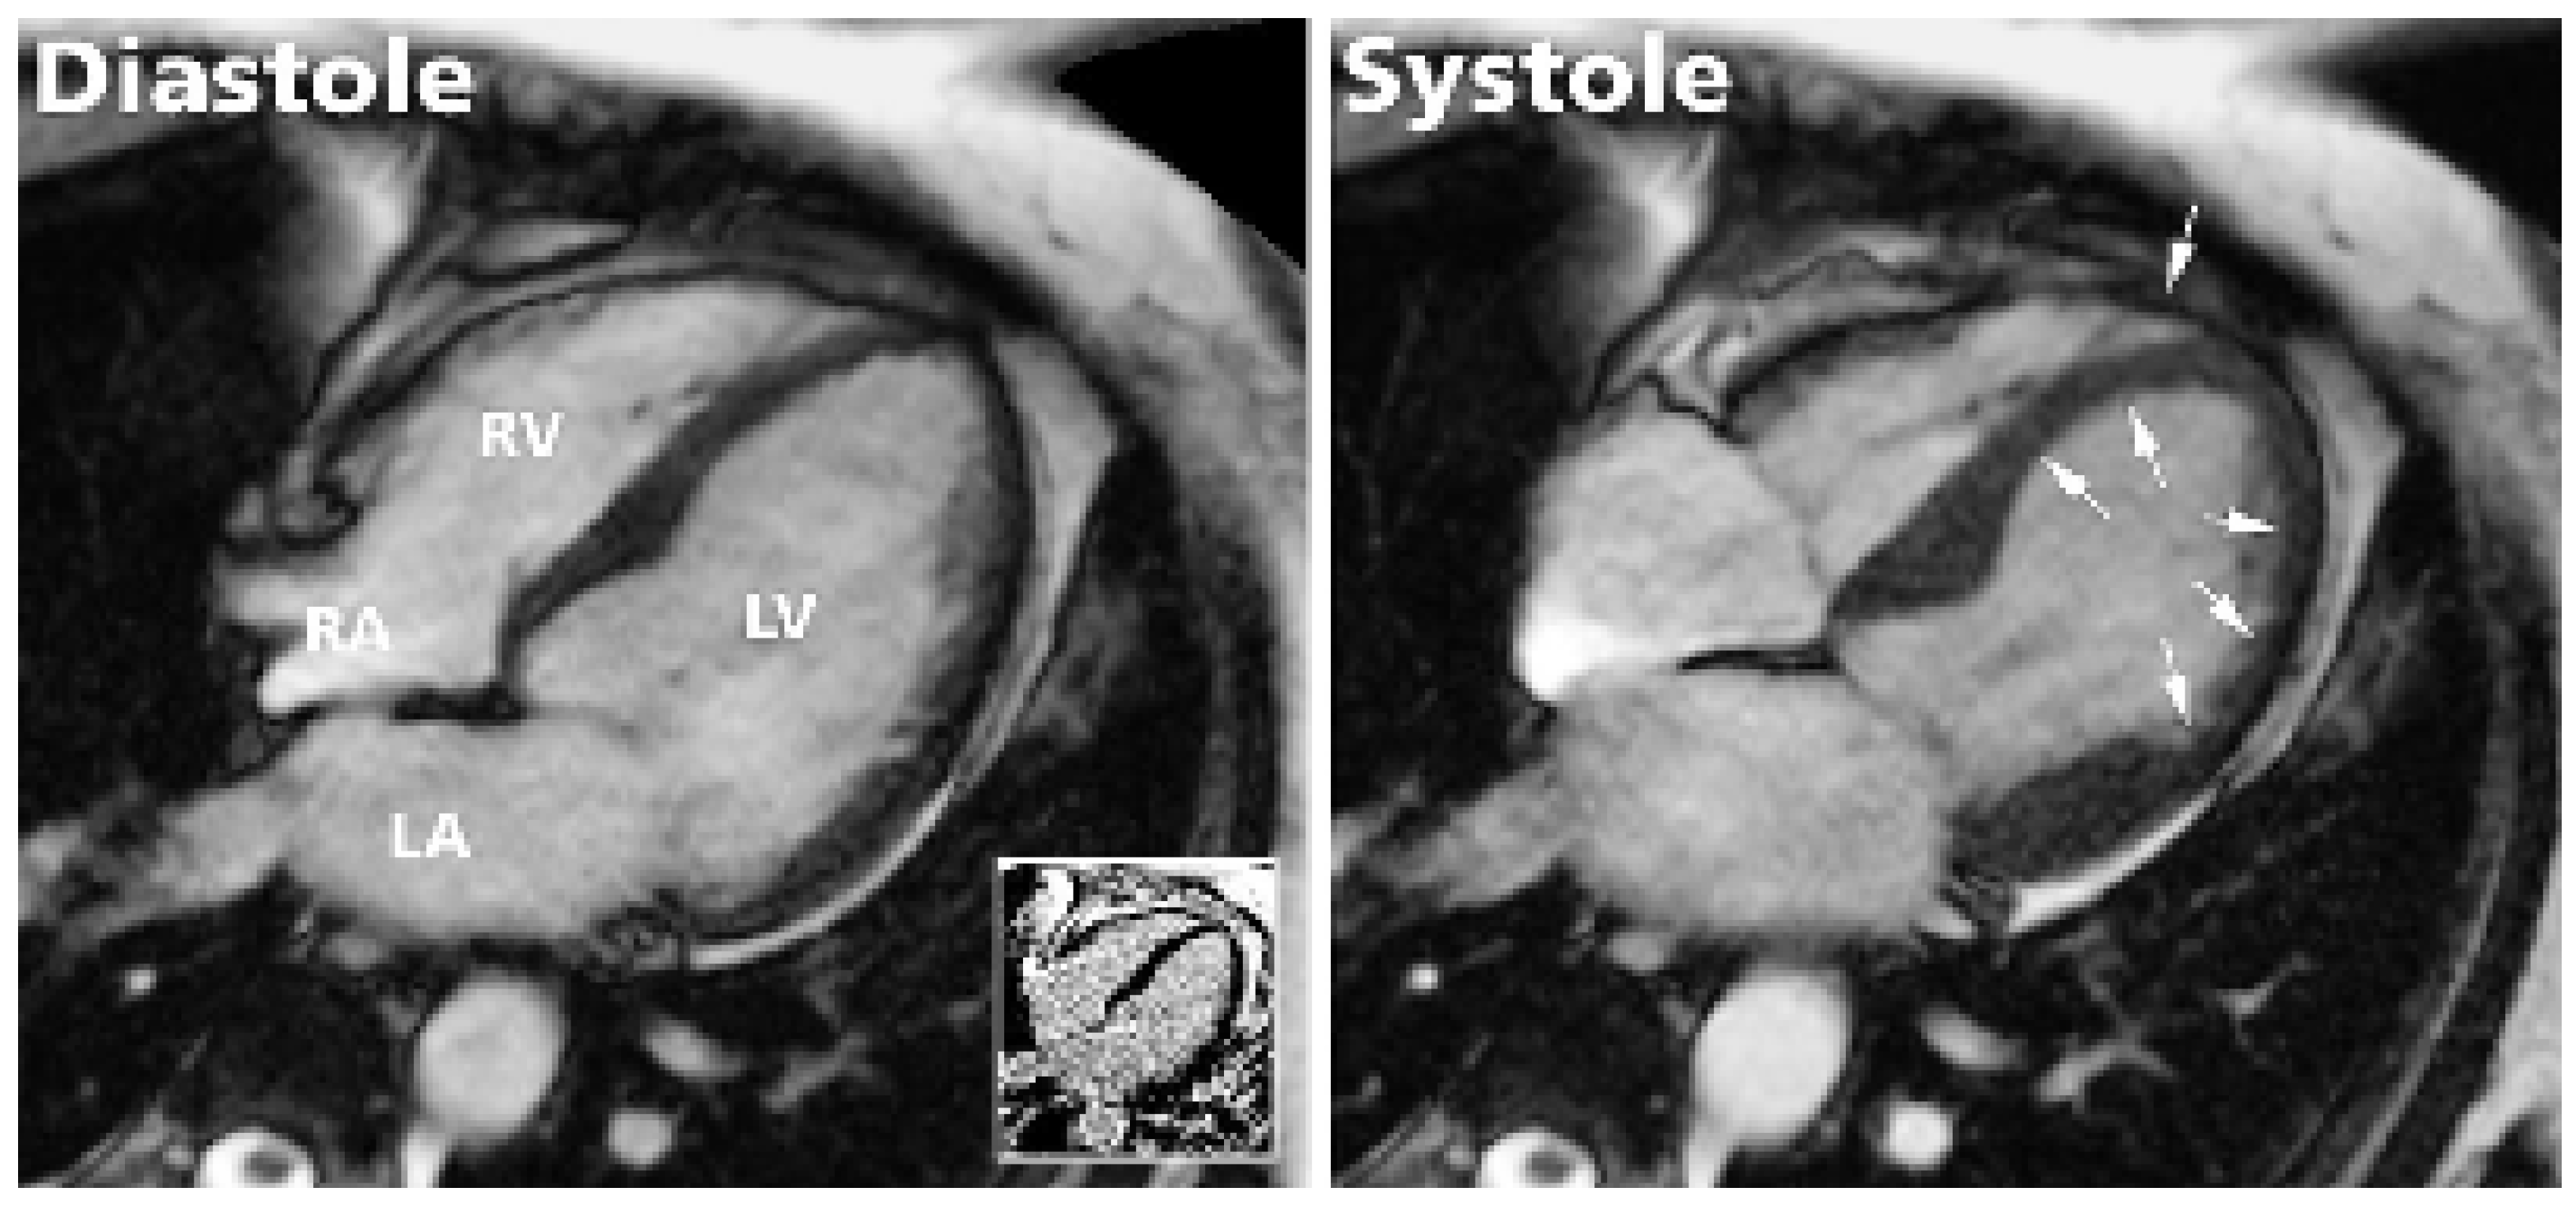

Zur Erhärtung der Diagnose und weiteren Abklärung wurde am Folgetag der Angiographie eine kardiale Magnetresonanz (CMR)-Untersuchung durchgeführt. Diese zeigte einen dilatierten linken Ventrikel mit eingeschränkter systolischer Pumpfunktion (EF 41%) bei Akinesie im gesamten midventrikulären Bereich, Hyperkontraktilität basal und erhaltener Kontraktilität apikal (Figure 4). Obwohl etwas weniger gut bekannt, scheint dieser Befund nicht ganz ungewöhnlich zu sein, bestanden doch auch in einer grösseren Serie bei 40% der Patienten apikal normale Kontraktionen [2]. Interessanterweise fand sich bei unserer Patientin zusätzlich eine Hypo- bis Akinesie des rechten Ventrikels (apikal), was in anderen Publikationen nicht erwähnt wird, jedoch gut zum gleichzeitigen Befall verschiedener Gefässterritorien passt.

Figure 4. Die kardiale Magnetresonanz-Untersuchung zeigte einen dilatierten linken Ventrikel mit eingeschränkter systolischer Pumpfunktion (EF biplan 41%) bei Akinesie im gesamten midventrikulären Bereich und guten Kontraktionen basal und apikal (Pfeile) sowie einen minimen Perikarderguss. Zusätzlich fand sich eine apikale Hypo- bis Akinesie des rechten Ventrikels (Pfeil). Im «late enhancement» (weiss-umrandete kleine Box) ergab sich kein Nachweis einer Narbe oder Fibrose. LV = linker Ventrikel, LA = linker Vorhof, RV = rechter Ventrikel, RA = rechter Vorhof.